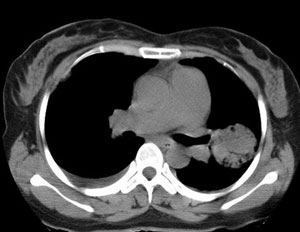

女性,30岁。

病史为胸痛20多天,无畏寒发热,无消瘦,无咳嗽咳痰。总之症状很逍遥。

临床以胸痛待查收住入院。

双肺野可见散在大小不等结节及肿块影,内密度不均匀,边缘部分清,部分欠清,纵隔未见明显肿大淋巴结.右侧胸腔少理积液.结合临床,考虑韦格肉芽肿可能吧,巨淋巴增生,结节病,特殊感染都要考虑.转移瘤临床不象.

本病例特点如下:

1.青年女性,以胸痛20多天就诊,无呼吸道及感染临床症状体征,无原发肿瘤病史;

2.肺ct表现为两肺多发大小不等结节影,大结节位于肺尖部,小结节多位于肺外带胸膜下,大结节内可见支气管充气征,周围可见月晕征(指在结节状或肉芽肿样病灶周围呈环形磨玻璃影),右肺门及腔静脉后可见小淋巴结,右侧胸腔内少量液体。

两肺散在分布大小不等的肿块及结节影,边缘毛糙,有分叶、毛刺,病灶密度不均匀,可见支气管充气相与空泡征。病变大多位于胸膜下,可见胸膜凹陷及胸腔积液。气管腔静脉间可见小结节影。